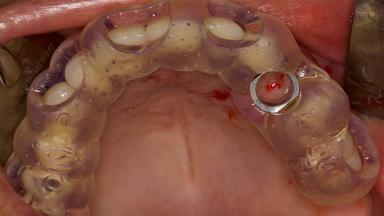

In this short microlearning module on digitally guided sinus floor elevation, we delve into a specialized aspect of the digital workflow for implant-guided surgery, focusing on the use of digital guides in the sinus floor elevation technique.

• explore the intraoperative use of digital guides in SFE